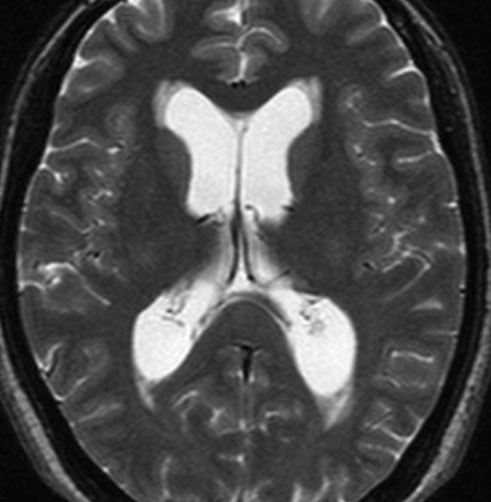

30代の女性に発生した髄膜腫です,一見すると松果体細胞腫と見分けはつきません。右の画像に見られるように典型的な中脳水道狭窄を生じていました。

軽度の閉塞性水頭症もありますが,頭痛も無く無症状なので経過を観察しました。髄膜腫だと診断できるのは,右の画像で見られるようにガレン大静脈が右側に偏っているからです。松果体細胞腫の場合は,ガレン大静脈は上方に変位します。

1年間経過観察したら水頭症が進行して脳室が拡大,腫瘍のサイズも大きくなりました。右側の画像で見られるようにガレン大静脈の左側のテントの下面から発生した髄膜腫でした。

左は手術直後の画像です,手術は左側のテント下面を見るために,後頭部経テント法 OTA occipital transtentorial approach で,小脳テントの左側を切断して腫瘍を全摘出しました。右側は6年後の画像ですが,腫瘍再発はありません。